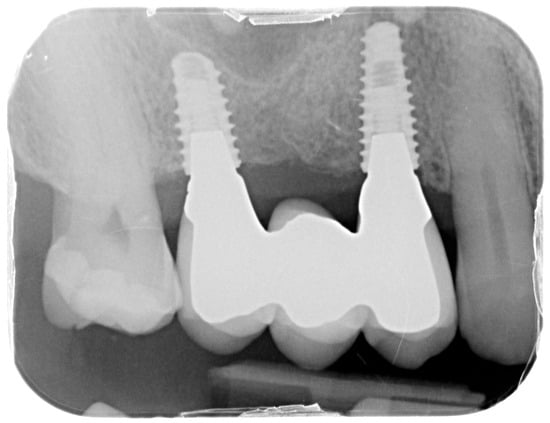

Healing abutments were screwed to the implants and the flaps were sutured. Additional peri-implant plastic surgery procedures (connective tissue grafts or free gingival grafts) were performed when needed in order to have at least 2 mm of attached keratinized mucosa. The prosthetic phases began upon healing of the soft tissues, and definitive screw-retained prostheses were finally delivered (Figure 11, Figure 12 and Figure 13).

For the evaluation of the mesial and distal MBL, intraoral digital radiographs were taken using the long-cone paralleling technique with the central beam directed to the alveolar crest. Periapical radiographs were taken at the delivery of the prosthesis and after 1 year of prosthetic loading (T2). The mesial and distal MBL, i.e., the distance between the top of the implant shoulder and the first visible bone-to-implant contact, were measured at the mesial and distal aspect with a 10–15× magnification using an image analysis programme (ImageJ v 1.49, NIH, Bethesda, MA, USA). The length of the implant was used as known measure for the calibration and determination of the exact magnification and distortion of the images. All measurements were performed by two examiners to the nearest 0.1 mm. In case of disagreement, the evaluation was re-done and results discussed until an agreement was found.

The status of peri-implant hard and soft tissues was assessed at T2, one year from the prosthetic loading. Data of 17 participants and 25 surgical sites were available, as one drop-out was recorded. The patient moved to another city and was not available for the follow-up recall. The overall mean MBL considering both mesial and distal aspects was 0.54 ± 0.7 mm. The mean BoP rate was 38.1%, while the mean PPD was 2.79 ± 0.78 mm with a maximum value of 4.5 mm. There were no statistically significant differences in MBL, PPD, BoP, or KMW based on BBT (p > 0.05). The correlation between BBT and clinical outcomes was weak and not statistically significant. Specifically, thicker buccal bone was associated with a slight reduction in PPD (coefficient: −0.33), but this effect was not statistically significant (p > 0.05). In contrast, BoP was strongly associated with increased PPD (coefficient: 1.04, p < 0.001), indicating that patients with higher BoP scores tended to have deeper PPD. There was no significant effect of KMW on PPD (p > 0.05).

Figure 12. Intraoral X-ray at delivery of the final prosthesis.

Medicina 61 01814 g012

Figure 13. Intraoral X-ray at one year follow-up.

Medicina 61 01814 g013